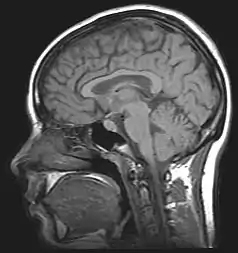

Il n'existe aucune cause directe connue de l'apotemnophilie. Cependant, de récentes recherches médicales montrent que l'apotemnophilie est liée à des anormalités du cortex préfrontal. Les apotemnophiles montrent des traits similaires concernant un désir d'amputation dès le jeune âge.